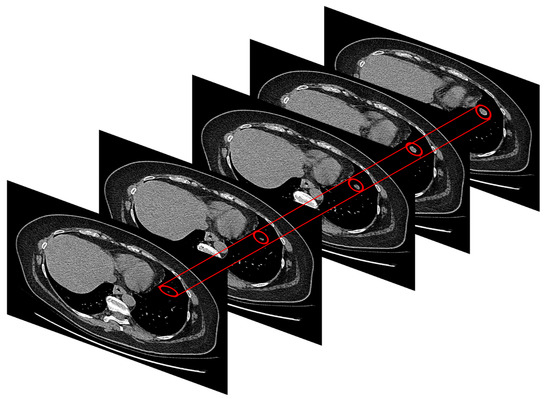

Figure 5 shows this phase performed in this block.

Figure 5.

The semi-automatic segmentation task for extracting the identified TARGET lesion for each CT-scan slice.

As shown in Figure 5, in the present block of the proposed pipeline, the authors after having identified the TARGET lesion to be monitored, perform a manual segmentation of the lesion starting from the first slice in which it is visible and up to the last one in which it disappears. In this way, a region of interest (ROI) of size 40 × 40 containing the only lesion to be processed were able to be extracted. Basically, both the first slice in which the lesion appears and the lesion itself (which therefore becomes the so-called target lesion according to RECIST criterion) is manually identified by the oncologist. Moreover, it is considered the last slice in which this lesion is evident. Then, using an ad-hoc developed software, the ROI surrounding the identified target lesion according to the chosen dimensions are selected. This ROI is maintained for each of the slices, up to the last identified as above. Therefore, the procedure is semi-automatic. Formally, this procedure can be modelled as follows:

where it has been indicated with Ij(x’, y’) the individual CT-scan slice which basically is a gray-level image (total number of slices equal to N) and with the corresponding gray-level ROI-image 40 × 40 extracted through the manual segmentation procedure Obviously, depending on each TARGET lesion and how extensive this is, the number of CT-scan slices to be processed varies for each patient, having regard also to the staging of the tumor. As is illustrated in the following block, this study proceeded to standardize this aspect, as is better described in the next section. Therefore, in conclusion, the output of this block is the series of gray-level images 40 × 40 characterizing the morpho-dynamic evolution of the identified TARGET lesion. Let define the common dimension of the selected image.